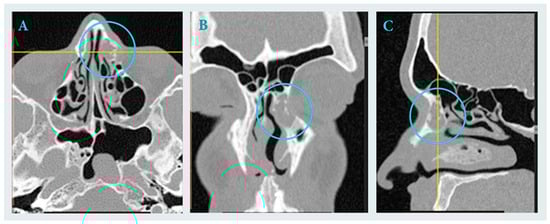

The study reports a diagnostic challenge involving an inflammatory lesion mimicking a brown tumor. A 23-year-old male patient was referred for treatment of a cystic lesion in the left frontal process of the maxilla and ethmoid region. The leading symptoms were hemoptysis and

The study reports a diagnostic challenge involving an inflammatory lesion mimicking a brown tumor. A 23-year-old male patient was referred for treatment of a cystic lesion in the left frontal process of the maxilla and ethmoid region. The leading symptoms were hemoptysis and chronic sinus inflammation. Endoscopic surgery was performed under general anesthesia, including curettage and drainage of the lesion into the middle nasal meatus. Histopathological examination revealed chronic inflammatory and fibrotic changes with hemosiderin deposits and CD68(+) histiocytes, findings that could suggest a brown tumor. However, subsequent laboratory investigations excluded this diagnosis. Postoperative healing was uneventful, with complete resolution of symptoms. This report highlights the importance of distinguishing inflammatory from metabolic bone lesions in the paranasal sinuses and underscores the critical role of histopathological evaluation in differentiating true neoplasms from inflammatory pseudotumors.

Figure 1